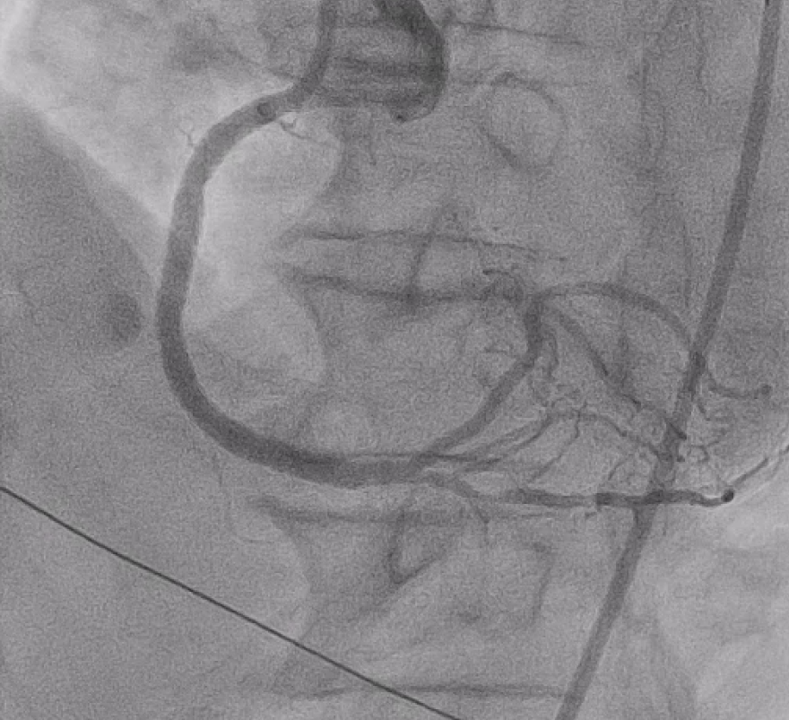

Right distal radial artery was used for access with a 6 Fr JR 3.5 guiding catheter. Anticoagulation was given to keep ACT >250 seconds and dual antiplatelet therapy was continued. A Runthrough wire crossed the diffusely calcified RCA lesion from proximal to distal. Sequential predilation with 2.0–3.0 mm non-compliant balloons was performed to assess vessel compliance.IVUS showed heavy concentric calcification with a minimal lumen area of 3.3 mm©÷. Calcium modification was done using a 4.0 ¡¿ 12 mm intravascular lithotripsy balloon with a total of 70 pulses, achieving good luminal expansion. Two drug-eluting stents were then implanted: 3.5 ¡¿ 50 mm at mid–distal RCA and 4.0 ¡¿ 24 mm at proximal–mid RCA, followed by high-pressure post-dilation up to 20 atm.After optimization, angiography revealed Ellis class II–III perforation at mid RCA. A 7 Fr system with Guideliner support was used for bailout. A 3.5 ¡¿ 19 mm covered stent was deployed to seal the perforation, followed by additional dilation. Because of residual contrast leakage, another 3.5 ¡¿ 16 mm covered stent was placed at proximal RCA, achieving complete sealing.Final IVUS confirmed good stent expansion and apposition. Angiography showed less than 30% residual stenosis with TIMI 3 flow.

Case Summary